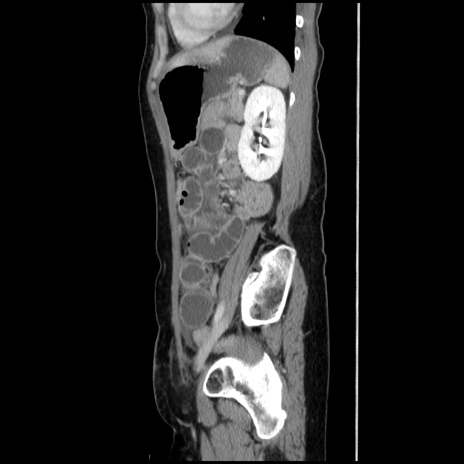

症例32(矢状断像)

【症例】40歳代 女性

【主訴】上腹部痛、嘔気・嘔吐

【現病歴】約9時間前頃から急に上腹部痛、嘔気、嘔吐が出現。改善しないため救急要請。

【既往歴】子宮頚癌(広汎子宮全摘術、放射線療法)、腸閉塞

【身体所見】腹部:平坦、軟、腸雑音亢進、上腹部を中心に腹部全体に圧痛あり。

【データ】WBC 8400、CRP 0.03